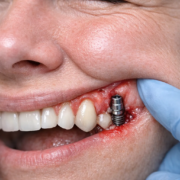

La péri-implantite est une inflammation des tissus autour d’un implant dentaire, associée à une perte progressive de l’os qui soutient l’implant.

Elle peut évoluer discrètement au début : repérer les symptômes tôt est le meilleur moyen d’éviter des complications.

À ne pas confondre avec la mucosite péri-implantaire : inflammation de la gencive autour de l’implant sans perte osseuse. La mucosite est considérée comme un précurseur/risque de péri-implantite.

Les symptômes les plus fréquents de la péri-implantite

1) Saignement autour de l’implant (au brossage ou au passage interdentaire)

C’est souvent le premier signe visible à la maison. En cabinet, le signe clé est le saignement au sondage (bleeding on probing).

2) Gencive rouge, gonflée, sensible autour de l’implant

La gencive peut paraître plus rouge, plus épaisse, et réagir au contact.

3) Pus ou écoulement (suppuration) + mauvais goût

Un écoulement (pus) ou un mauvais goût persistant est un signe d’infection locale et doit faire consulter rapidement.

6) Récession de la gencive, “implant plus visible”

La gencive peut se rétracter autour de l’implant (marge qui recule), donnant l’impression que “ça s’est creusé”.